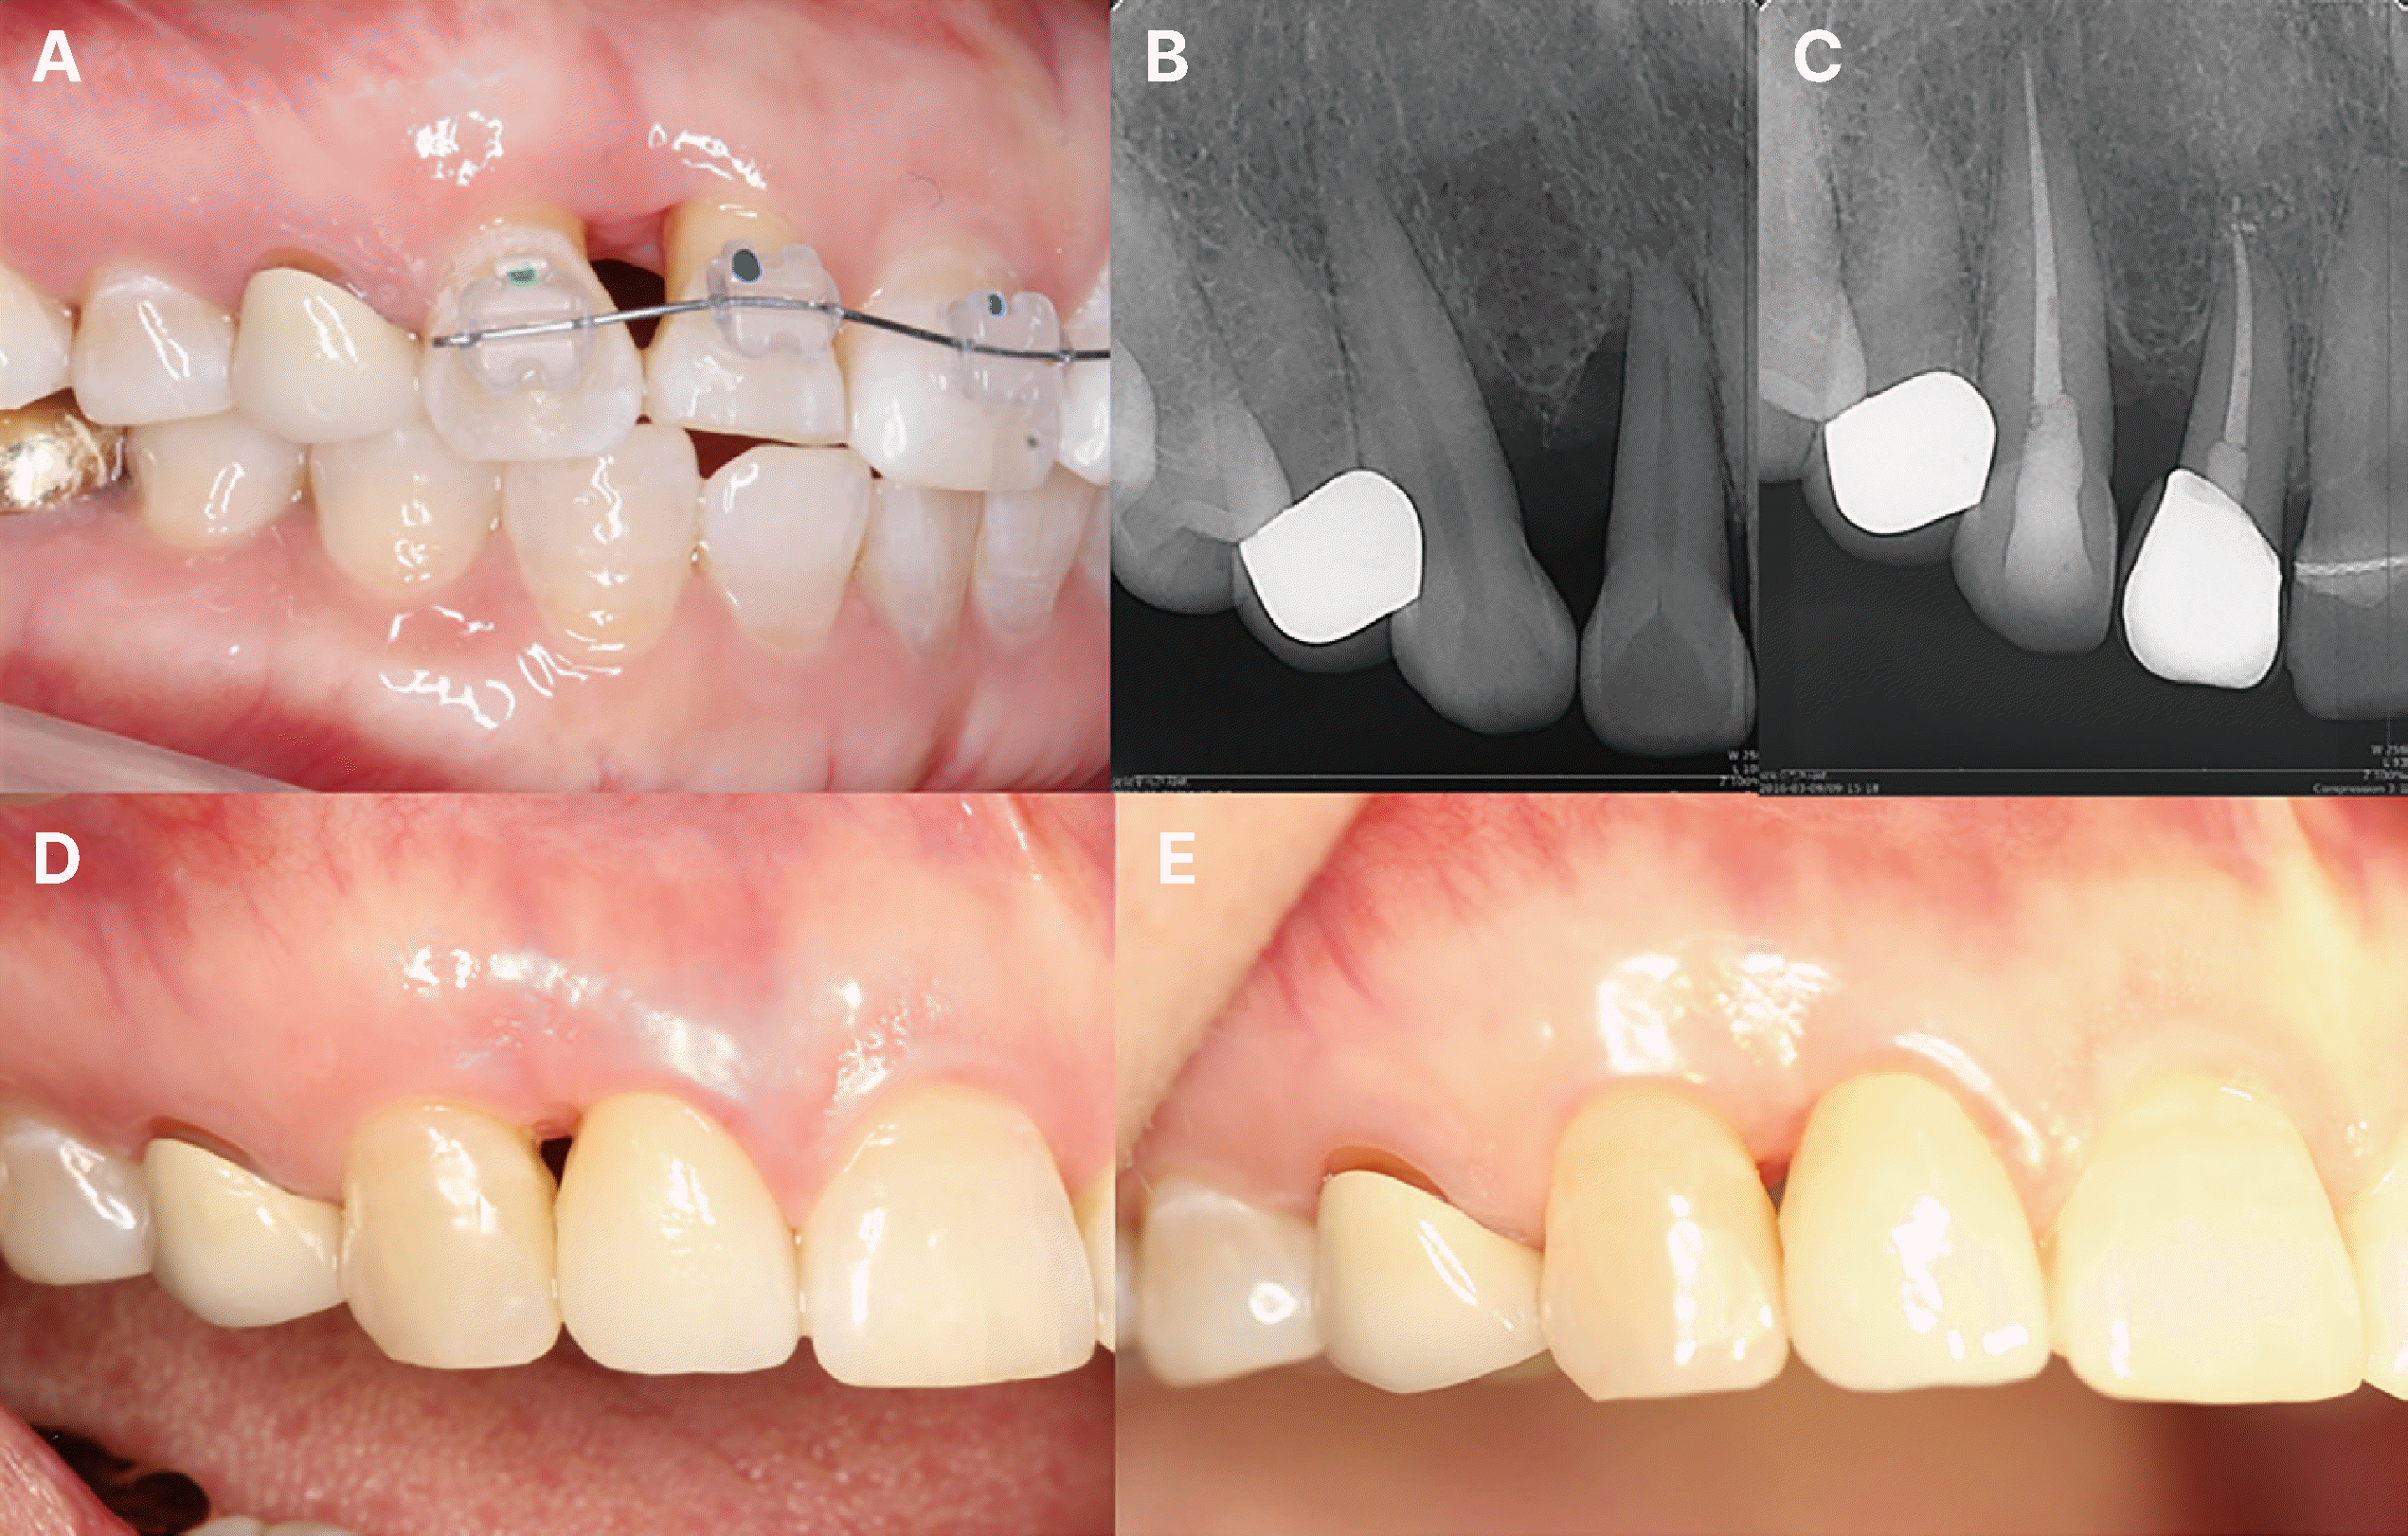

Fig. 4

Clinical presentation of papilla creeping by tooth approximation in case 2. After periodontal treatment (A), immediately before orthodontic treatment (B), after performing interproximal reduction, orthodontic treatment was started (C), and six months later after minor tooth movement of the maxillary anterior teeth (D). Modification of the tooth shape lowered the contact point, resulting in complete recovery of the interdental papilla.